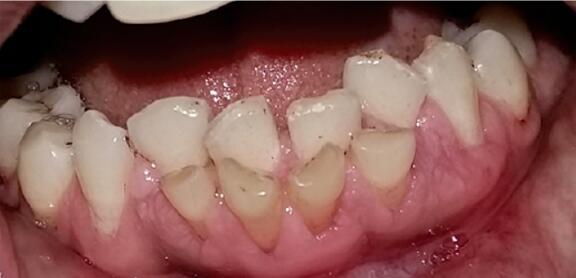

也有一些情况下,乳牙的牙根不被吸收,一直牢牢的把牙齿固定住,如果不拔出的话,会存留数十年,如下图所示。

图片来自参考文献[2]

为什么这些乳牙就不掉呢?咱们先看下正常情况下,乳牙怎么脱落的。